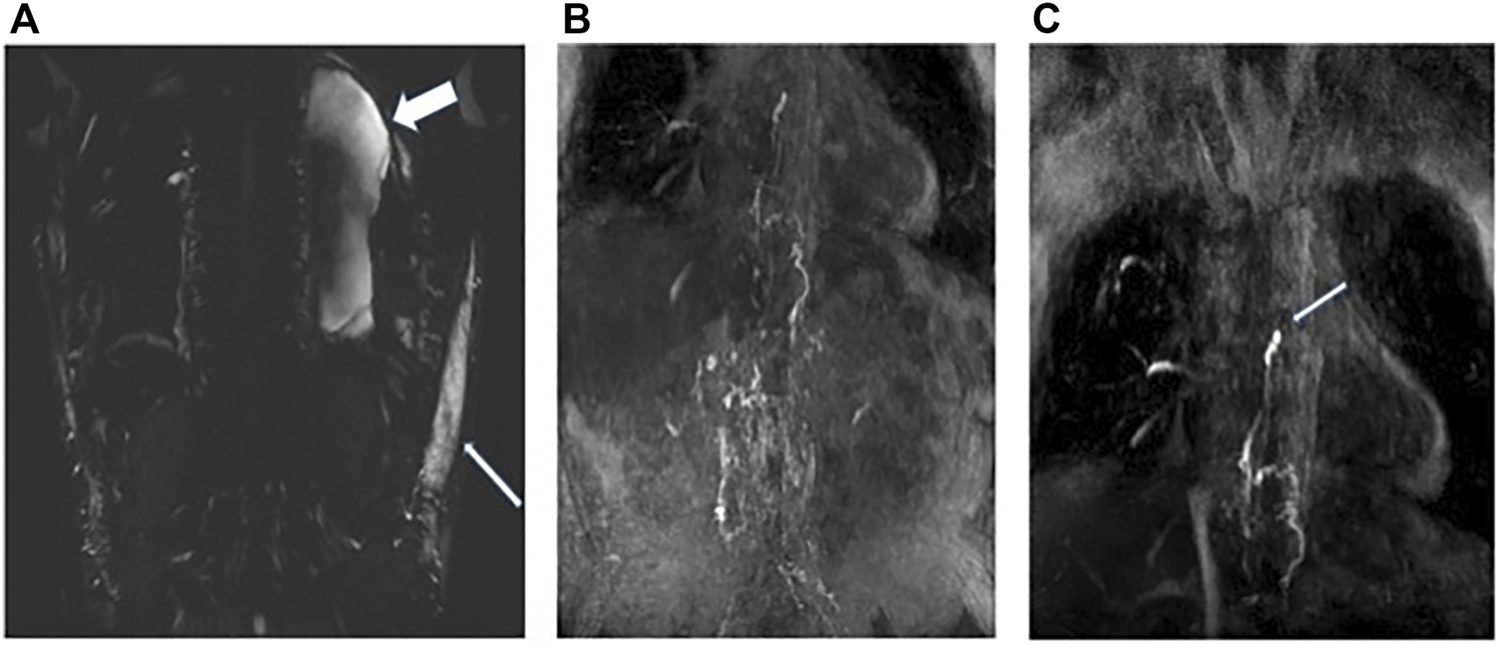

DCMRL was performed with intranodal injection of gadolinium into the inguinal lymph nodes on both sides (Figures 2A–C). Initial T2 weighted imaging was undertaken prior to contrast and demonstrated a moderate left sided pleural effusion (Figure 2A) and marked soft tissue oedema. At the time of imaging there was a right sided chest drain in situ. Scanning was then re-commenced as injection of 8 ml of a Gadolinium containing contrast agent, Dotarem [(gadoterate meglumine) (Guerbet, Raleigh, United States)] was carried out on each side at a rate of 1–2 ml/min. This demonstrated bilateral drainage of contrast from the iliac systems into the cisterna chylii (Figure 2B). The thoracic duct appeared interrupted which was in keeping with the history of surgical ligation of the thoracic duct (Figure 2C: White arrow). No single lymphatic channel was seen draining the abdominal lymphatics into the neck. No leakage of contrast was seen into the pleural cavity.

FIGURE 2

Patient A: (A) Heavy T2 weighted coronal MRI image demonstrating moderate left sided pleural effusion (wide white arrow) and soft tissue oedema (narrow white arrow). (B) Post contrast MRI coronal MIP image demonstrating bilateral flow of contrast from the inguinal lymph nodes into the retroperitoneal lymphatics and up into the distal thoracic duct. (C) Termination of the thoracic duct at the level of the carina (white arrow) at the site of surgical ligation. No single point of drainage into the terminal thoracic duct from the abdomen is identified. No leakage of contrast is seen into the pleural effusions.